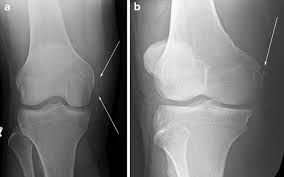

They are called the medial and the lateral femoral condyle, respectively. An imbalance of the muscles around the knee (some muscles are weaker than others.) overuse (repeated bending or twisting) of the knee joint, especially during sports. However, two of the patients had one or more fractures missed when they first presented. The medial femoral condyles are the bony protrusions on the inside edge of the bottom of the femur bone in each thigh. Osteochondritis dissecans (ocd) is an acquired, reversible, idiopathic lesion. Osteonecrosis of the medial femoral condyle presents as a sudden onset of pain on the medial side of the knee. This is associated with a positive bone scan and, frequently, a radiolucent lesion in the subchondral zone. Methods sixteen knees with a small medial femoral. The medial condyle is larger than the lateral (outer) condyle due to more weight bearing caused by the centre of mass being medial to the knee. Medial condyle of femur from wikipedia, the free encyclopedia the medial condyle is one of the two projections on the lower extremity of femur, the other being the lateral condyle. Root tear (radial tear) of the medial meniscus mild or moderate knee arthritis Osteonecrosis of the medial femoral condyle can be treated in a variety of ways depending on the stage of the disease. Of the six patients who had suffered an isolated fracture of their medial condyle, four of the patients had their fractures diagnosed on the first visit.

The radiographs demonstrated abnormal contour of the medial femoral condyle, consistent with an osteochondral defect, and a fabella posterior to the knee. Methods sixteen knees with a small medial femoral. It acts to support a significant amount of the patient's body weight. An imbalance of the muscles around the knee (some muscles are weaker than others.) overuse (repeated bending or twisting) of the knee joint, especially during sports. If there is a fracture (break) in part of the condyle, this is known as a fracture of the femoral condyle. The medial femoral condyle is supplied by a plexus of vessels from the descending genicular artery and the medial superior genicular artery. Damage may also be the result of a direct blow to the knee. Palpable to either side of the knee joint when it is bent, they are known specifically as the medial and lateral femoral condyles.

An articular cartilage injury, or chondral injury, may occur as a result of a pivot or twist on a bent knee, similar to the motion that can cause a meniscus tear. An imbalance of the muscles around the knee (some muscles are weaker than others.) overuse (repeated bending or twisting) of the knee joint, especially during sports. Juvenile ocd lesions have a better healing prognosis than adults. Osteonecrosis of the medial femoral condyle presents as a sudden onset of pain on the medial side of the knee. The radiographs demonstrated abnormal contour of the medial femoral condyle, consistent with an osteochondral defect, and a fabella posterior to the knee. Please see our knee injury protocol for additional information on this topic. Chondral injuries may accompany an injury to a ligament, such as the anterior cruciate ligament. Medial condyle of femur from wikipedia, the free encyclopedia the medial condyle is one of the two projections on the lower extremity of femur, the other being the lateral condyle. In the knee, chondromalacia is usually related to injury, overuse of the knee, and poorly aligned muscles and bones around the knee joint. The motions of the condyles include rocking, gliding and rotating. One presumed mechanism of injury is a stieda fracture (avulsion injury of the medial collateral ligament at the medial femoral condyle). Generally, ocd seems to affect males more commonly than females (between 2:1 and 3:1). According to the hospital for special surgery, the medial femoral condyle is the inside of the knee, and health issues dealing with it can be treated.